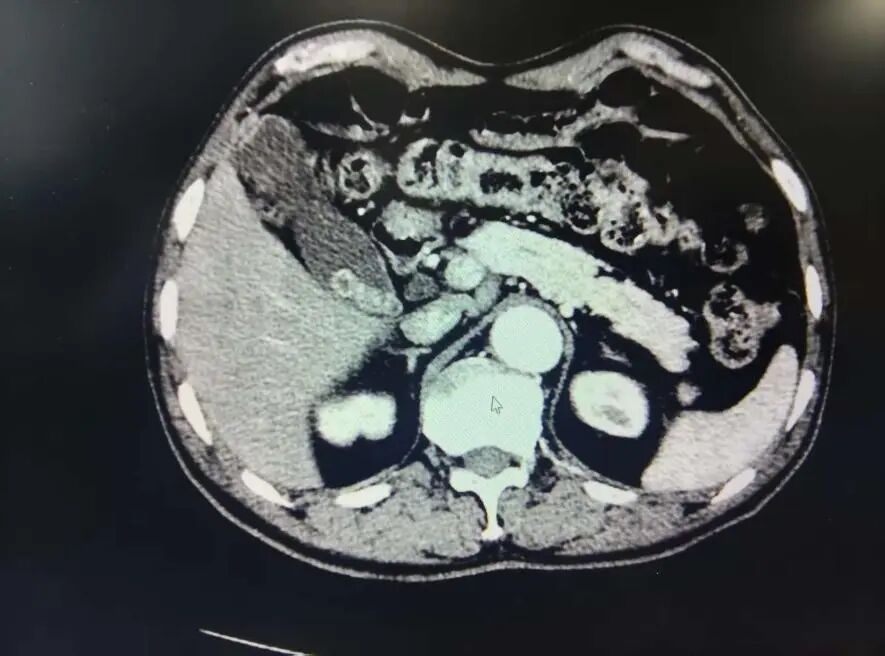

影像学检查提示患者胆囊多发结石、胆总管稍扩张,需排除梗阻可能。若采取腔镜下胆总管探查或ERCP治疗,均会延长麻醉时间、增加手术风险。

经过充分论证,团队决定在术中实施胆道造影,以明确胆总管情况,避免不必要的复杂操作,从而控制手术时间。同时,团队制定了详细的术中预案与应急措施,确保手术安全。

影像团队术中指导:参与术中造影,为手术决策提供了关键影像依据,明确了手术路径。